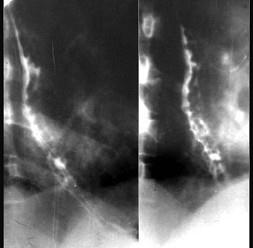

问题 下列各图最佳的诊断是 ( )

选项 A、食管静脉曲张 B、以上都不是 C、食管憩室 D、贲门失弛症 E、食管癌

答案 A